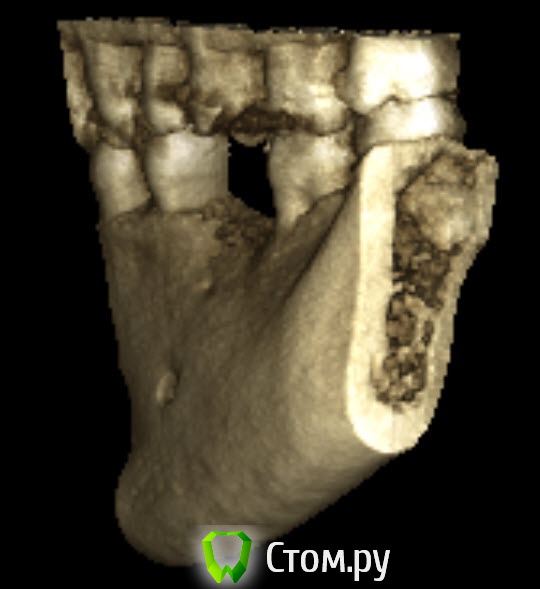

bobrdobr Опубликовано 18 февраля, 2014 Автор Поделиться Опубликовано 18 февраля, 2014 (изменено) Имплант был предложен Semados 4,1*11,5 без костной пластики. судя по фото, скорее всего нужна. От КТ нужен срез горизонтальной плоскости - вид сверху на костный гребень, на 1 мм ниже его вершины. Сейчас попробую. Прикладываю 4 снимка: на уровне гребня (как мне кажется) и на 1,2,3 и мм. ниже. Изменено 18 февраля, 2014 пользователем bobrdobr Ссылка на комментарий

Bier Опубликовано 18 февраля, 2014 Поделиться Опубликовано 18 февраля, 2014 Можно поставить, одновременно добавив немного кости и закрыть мембраной. Кость можно даже взять прямо из того места, куда будет ставиться имплантат, т.е. доп травмы не будет Ссылка на комментарий

bobrdobr Опубликовано 18 февраля, 2014 Автор Поделиться Опубликовано 18 февраля, 2014 Можно поставить, одновременно добавив немного кости и закрыть мембраной. Кость можно даже взять прямо из того места, куда будет ставиться имплантат, т.е. доп травмы не будетБольшое спасибо за мнение! Ровно такой вариант предлагал хирург 3 под винтовой имплант. Правда, он же предложил байкон Что будет, если кость не подсыпать и мембрану не ставить? Ссылка на комментарий

Bier Опубликовано 18 февраля, 2014 Поделиться Опубликовано 18 февраля, 2014 Может и ничего не будет, если широкий диаметр не выбирать и десну подсадить, а может десна немного отойдет вниз через годик-другой. Ссылка на комментарий

bobrdobr Опубликовано 18 февраля, 2014 Автор Поделиться Опубликовано 18 февраля, 2014 Все ясно, благодарю. Диаметр 4,1 мм предлагают (Semados). Нормально для жевательного зуба? Ссылка на комментарий

Bier Опубликовано 18 февраля, 2014 Поделиться Опубликовано 18 февраля, 2014 Тогда подсыпать однозначно нужно, 4,1- стандартная платформа. Лучше сюда ставить тонкую платформу. Неважно какой зуб, они держат нагрузку. Главное чтобы кость была вокруг имплантата. Ссылка на комментарий